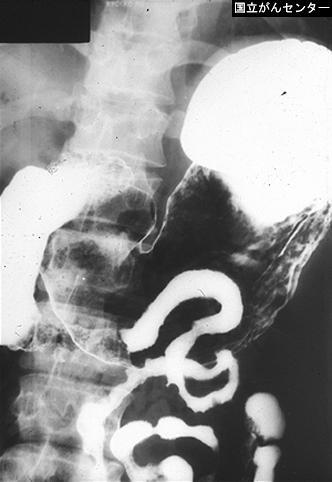

Estrongiloidiasis que compromete prácticamente todo el Intestino Delgado (caso de la década del 1960)

Tokyo Pref., Centro Nacional de curaciones de Cáncer, Hospital Central y Centro Kyusyu de Curaciones de Cáncerc

Enfermedad Parasitaria/Estrongiloidiasis

intestino delgado/mas de dos

método de exámen

Rayos X

40 -